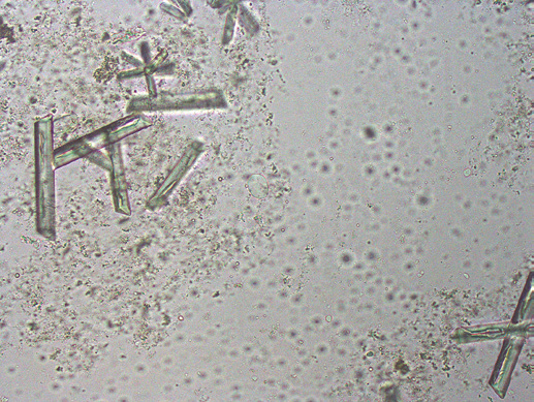

图28 鸟粪石晶体(未染色尿沉渣)。可以看到几个具有三维结构的鸟粪石晶体。还有些晶体呈针状,其他许多晶体无固定形状。背景中的小圆细胞未对焦,很可能是红细胞。用数码相机通过显微镜目镜拍摄的图像。图片来自Dr. Felipe Galvao, Downers Grove, IL。